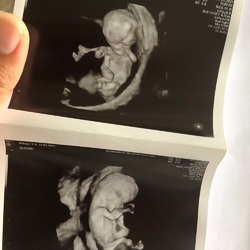

Inderdaad. Als je het eigenlijk niet meer verwacht. Verloskundige vertelde ook na een goed hartje met 8 weken je eigenlijk van het goede mag uitgaan.